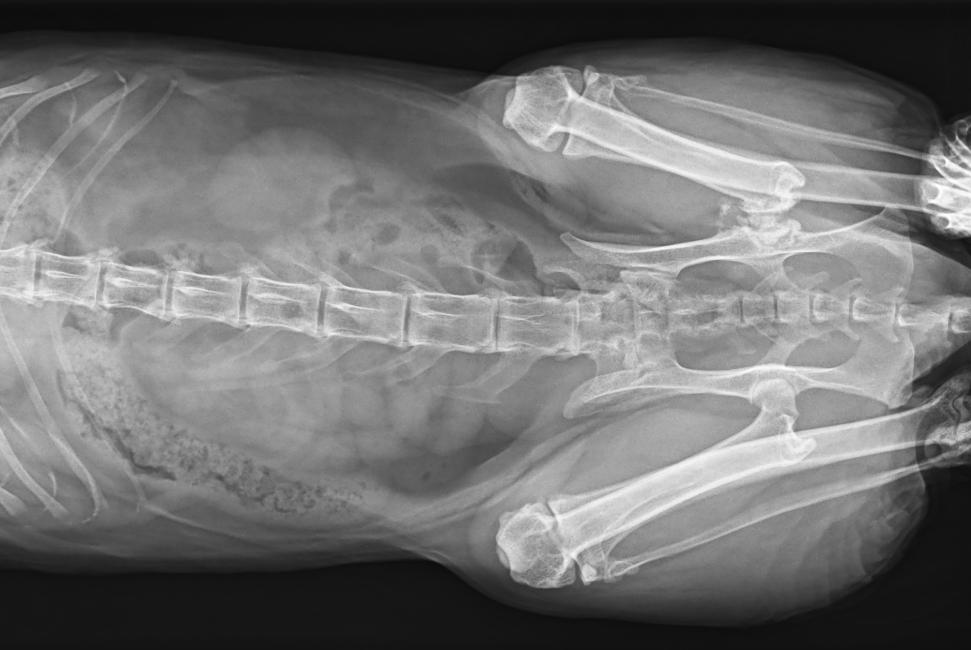

● 17*17大尺寸平板探測(cè)器,獲得高質(zhì)量圖像

● 優(yōu)異的空間分辨率及信噪比,提升圖像質(zhì)量

● 采用線噪聲消除技術(shù),使成像質(zhì)量提升40%

● 智能高效的圖像處理軟件,大幅提升圖像質(zhì)量

● 可浮動(dòng)床面設(shè)計(jì),滿足大部分中小型寵物檢查